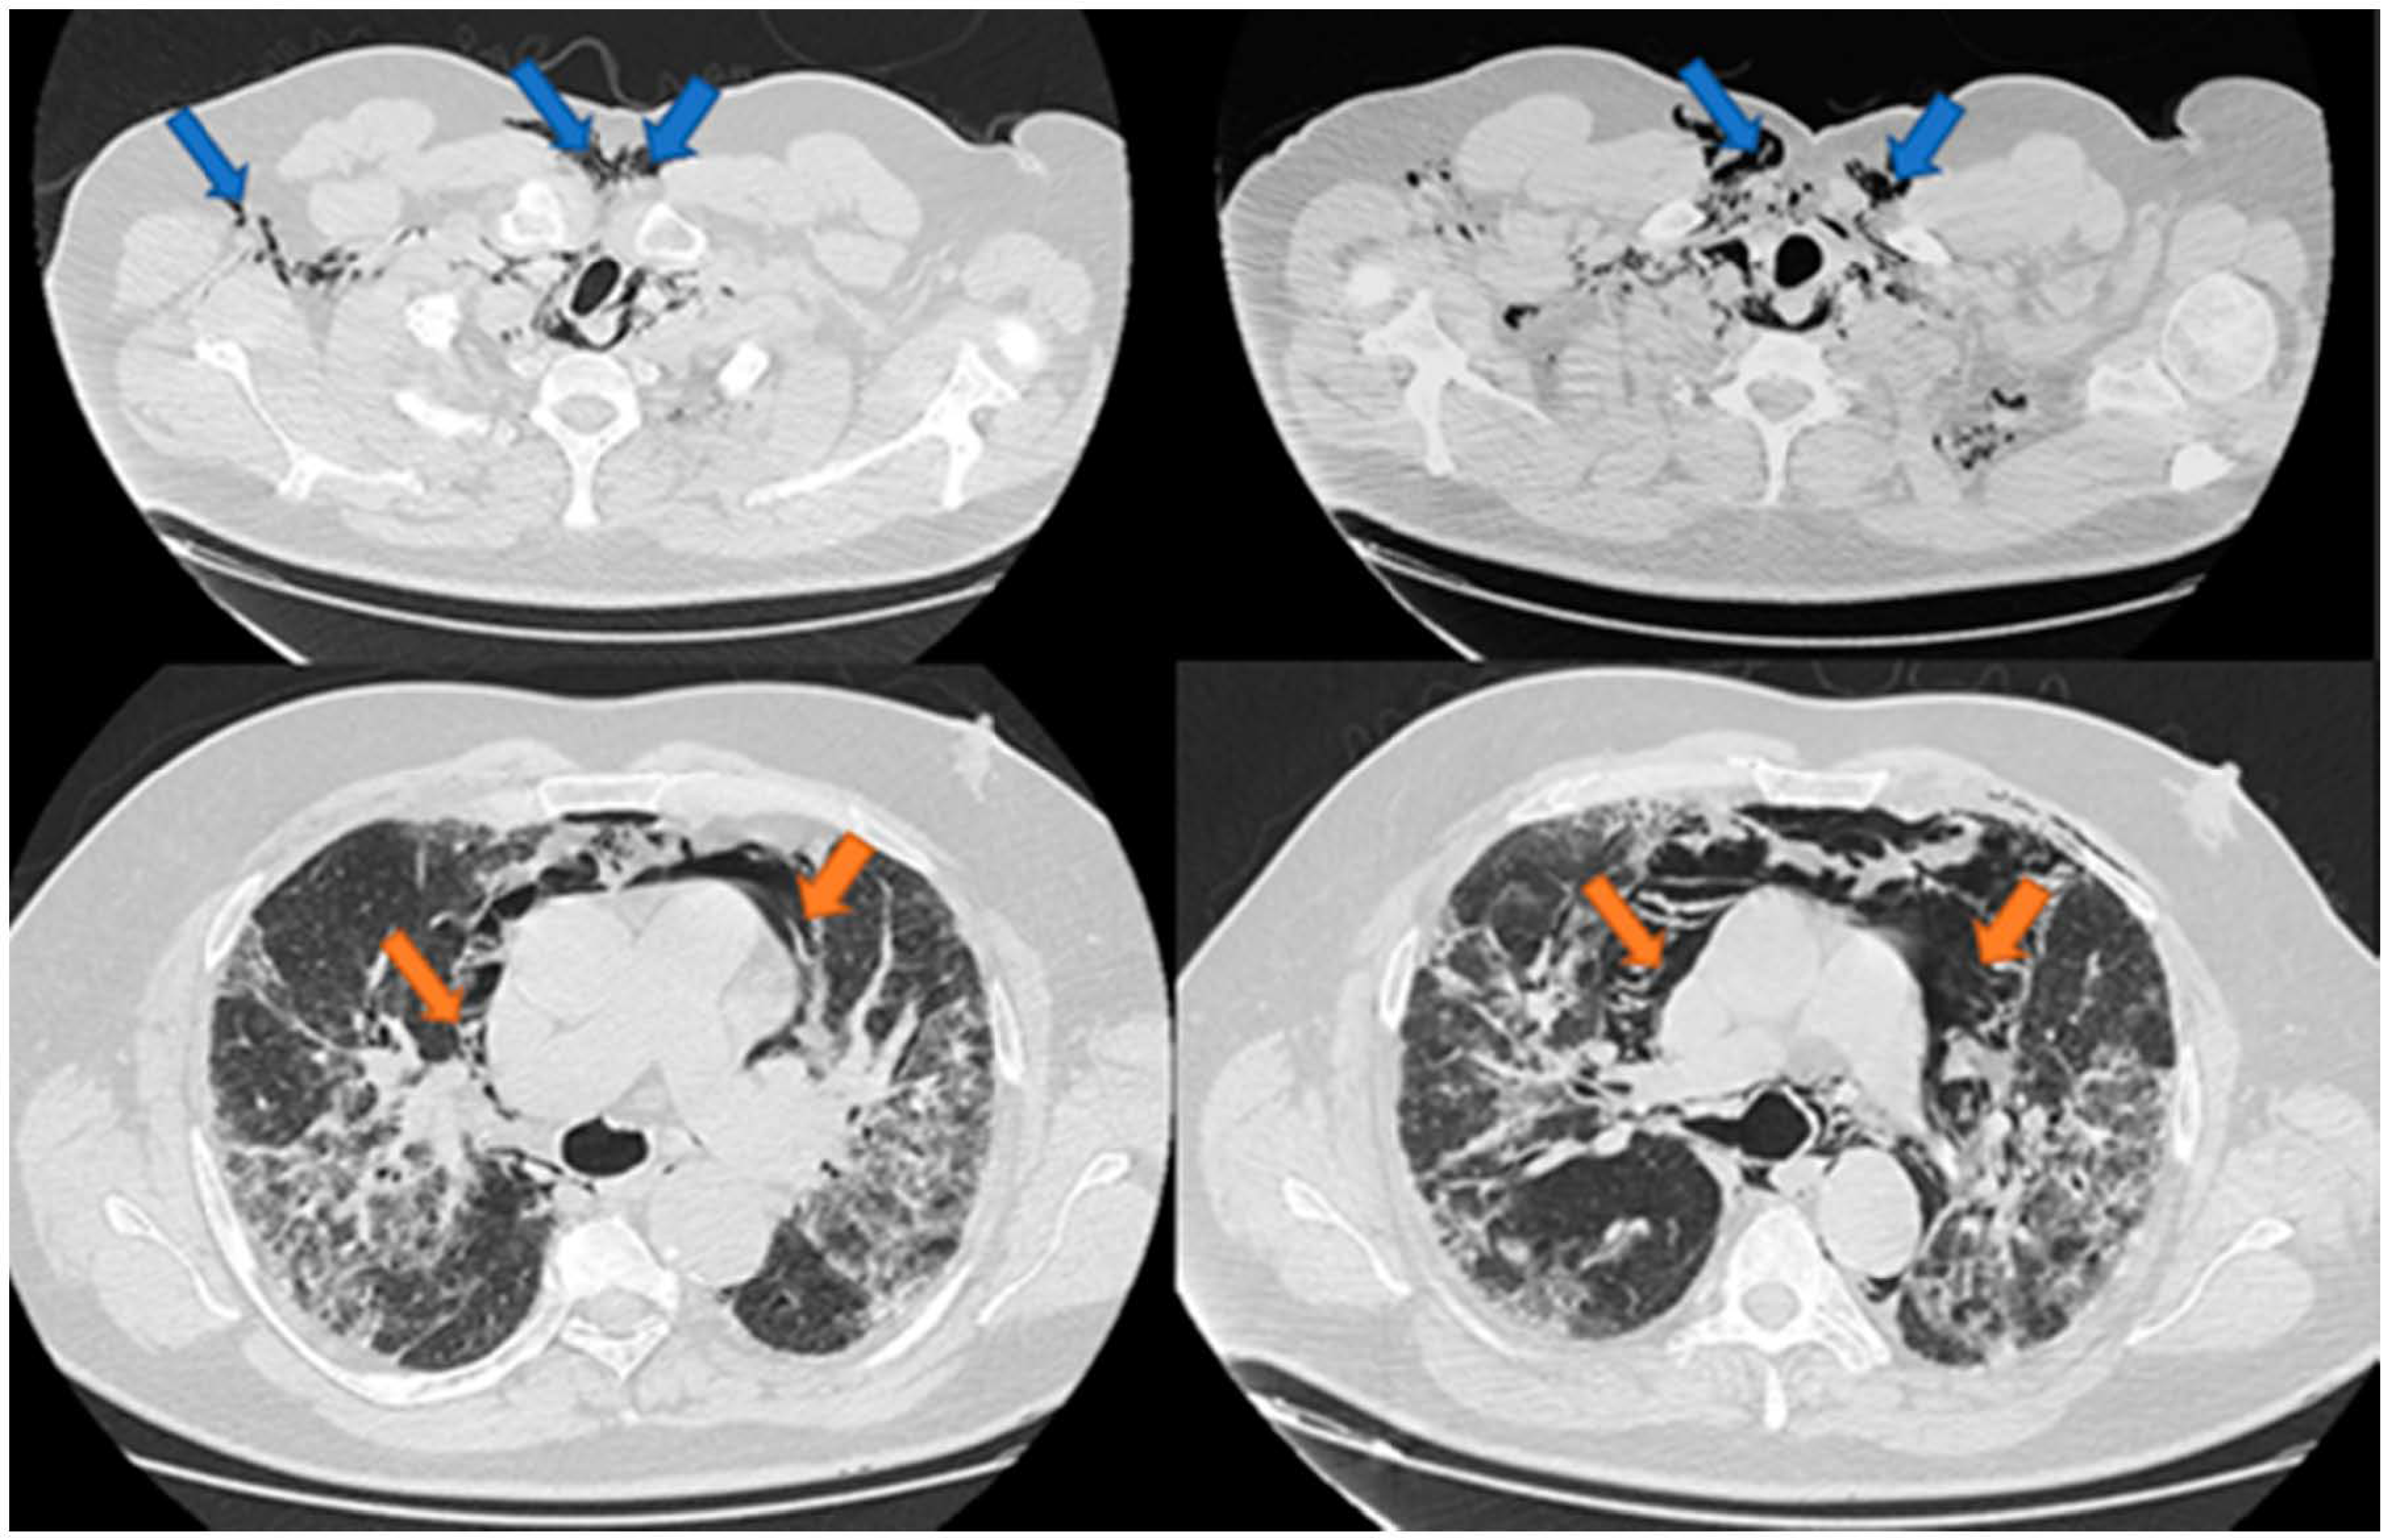

Spontaneous Pneumomediastinum, Pneumothorax, Pneumopericardium and Subcutaneous Emphysema—Not So Uncommon Complications in Patients with COVID-19 Pulmonary Infection—A Series of Cases

3. Results